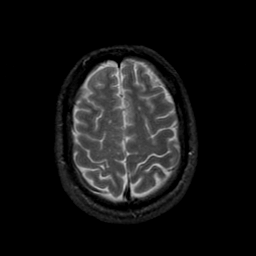

MR Study #23, January 26, 1992 -- Slice #40